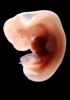

Carnegie Stage 17 (41 post-ovulatory days)

Most embryos at stage 17 are approximately 41 postovulatory days old and measure 11-14 mm in length. Distinguishing criteria for this stage include distinct digital rays in the hand plate, a rounded digital plate in the foot, a complete complement of hillocks on the mandibular and hyoid arches, distinct nasofrontal grooves, and a slight indication of a lumbar curvature.

This specimen does not represent normal development. The caudal nueral tube has failed to close properly.